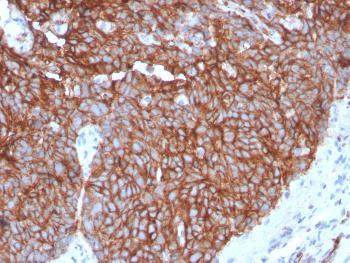

It stains normal mesothelial cells as well as epithelial mesotheliomas in a thick membrane pattern due to abundant lung microvilli on the surface of these cells. It stains normal mesothelial cells as well as epithelial mesothelimias in a thick membrane pattern due to abundant lung microvilli on the surface of these cells. Cells were grown on chamber slides and fixed with formaldehyde prior to staining.

• Calretinin Antibody Biocare Medical